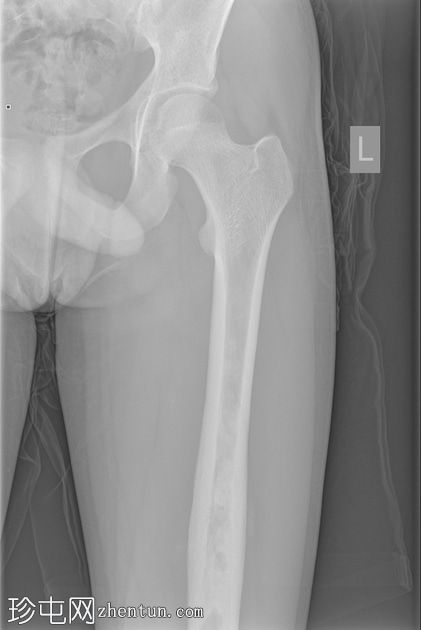

X光片

正面

侧面

斜面

左股骨中段可见边界不清的硬化区域,伴有宽阔的过渡区和虫蛀状外观。

邻近软组织可见小块钙化灶。无骨折或脱位。